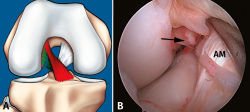

La reconstrucción selectiva del fascículo afectado sigue los principios básicos de la reconstrucción clásica anatómica del LCA (Figuras 9 y 10). Los autores realizan 3 portales: un portal anterolateral, lo más proximal posible con el fin de evitar la almohadilla grasa infrapatelar de Hoffa y tener una visión panorámica de toda la articulación; un portal AM alto y parapatelar, que utilizaremos como portal de visión y que nos va a permitir una mejor visualización de la huella anatómica femoral; y un portal AM accesorio, lateral al cóndilo femoral medial e inmediatamente superior al menisco interno, desde donde realizaremos el brocado del túnel femoral mediante técnica de manos libres(8). Otros autores recomiendan la realización del túnel femoral mediante técnica outside-in, considerando que ello facilita la realización del brocado femoral sin dañar las fibras del fascículo intacto(4).

Figura 10. Plastia de reconstrucción selectiva unifascicular (fascículo posterolateral –PL–). A: imagen artroscópica de la rodilla izquierda desde el portal anterolateral. Se evidencia una rotura completa crónica del fascículo PL con remanente tibial (flecha) e integridad del fascículo anteromedial (AM); B: imagen artroscópica de la rodilla izquierda desde el portal anterolateral. Colocación de la guía tibial tomando el remanente como referencia en una reconstrucción selectiva del fascículo PL; C: imagen artroscópica desde el portal AM que muestra la plastia de reconstrucción selectiva-aumentación del fascículo PL con autoinjerto de isquiotibiales (flecha).

Técnicamente, en la reconstrucción selectiva del fascículo AM o PM es fundamental reproducir la huella anatómica, tanto en el fémur como en la tibia. La mejor referencia para conseguir una posición correcta es localizar el remanente del fascículo roto(33).

Diferentes tipos de injerto pueden ser seleccionados, tanto autoinjerto como haloinjerto, según la preferencia de cada cirujano. Los autores utilizan preferentemente los tendones de la pata de ganso (autoinjerto), habitualmente de 7-8 mm de diámetro. Calibres superiores pueden llenar en exceso el espacio intercondíleo y comprometer tanto el fascículo preservado como la extensión de la rodilla. Los injertos con taco óseo también pueden ser utilizados, pero se desaconseja su uso por la mayor dificultad a la hora de pasar los mismos a través de los túneles y la mayor probabilidad de destruir el remanente ligamentoso(2,19).

En cuanto a los dispositivos de fijación del injerto, los autores utilizan un sistema de fijación suspensoria ajustable en el fémur y un tornillo interferencial en la tibia, normalmente 1 mm superior al calibre del túnel brocado. Para la reconstrucción selectiva del fascículo PL, fijamos el mismo a 0° para minimizar el riesgo de rerrotura y, para el fascículo AM, lo fijamos a unos 20°, en ambos casos pretensionado y sumergido en una solución antibiótica con vancomicina para minimizar el riesgo de infección(34).